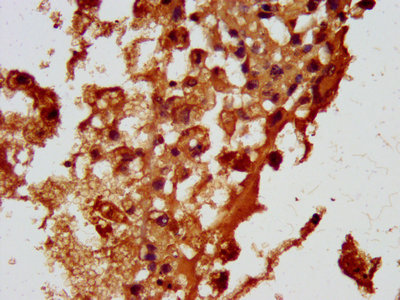

IHC image of CSB-PA857429LA01HU diluted at 1:100 and staining in paraffin-embedded human melanoma performed on a Leica BondTM system. After dewaxing and hydration, antigen retrieval was mediated by high pressure in a citrate buffer (pH 6.0). Section was blocked with 10% normal goat serum 30min at RT. Then primary antibody (1% BSA) was incubated at 4°C overnight. The primary is detected by a biotinylated secondary antibody and visualized using an HRP conjugated SP system.